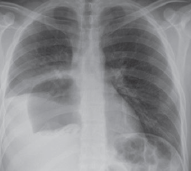

Pablo Marcos-Santos, Francisco Javier Tejero-Pintor, Javier Sánchez-González, Patricia Callejo-Pérez, David Pacheco-Sánchez

|